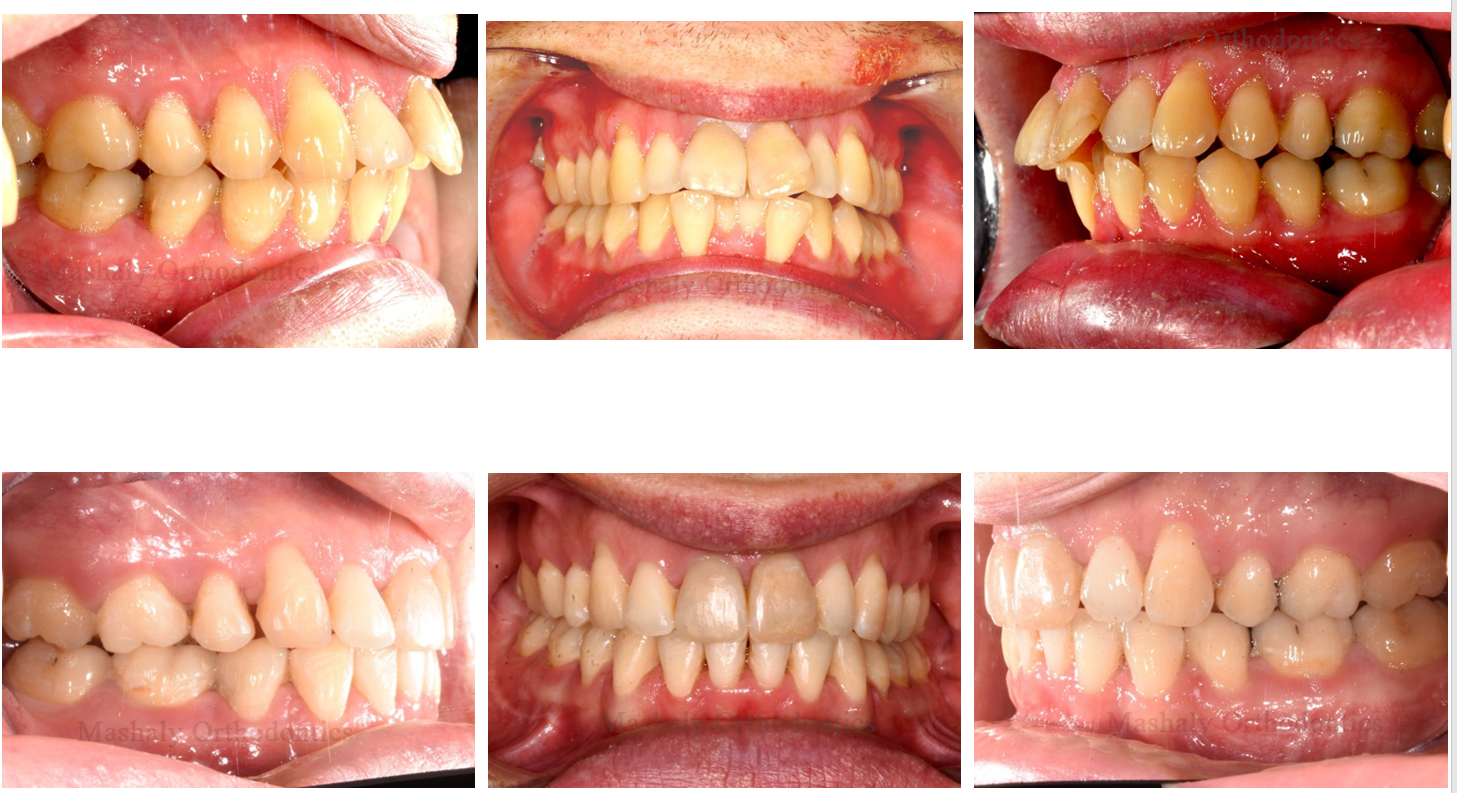

Orthodontics is a dental specialty that helps treat misalignment of teeth, malocclusion

(improper bite), and other related issues. Orthodontic treatment goes beyond addressing cosmetic concerns and is also used to treat various medical conditions such as impacted teeth and other dental problems.